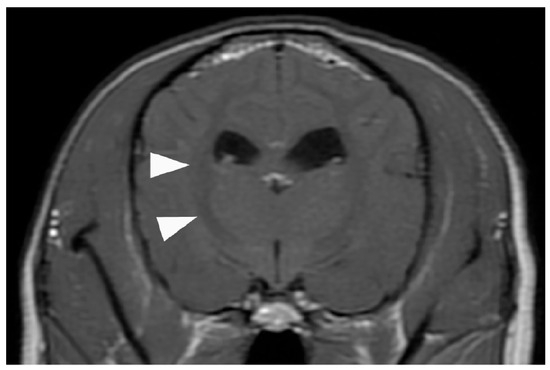

2. Case Presentation